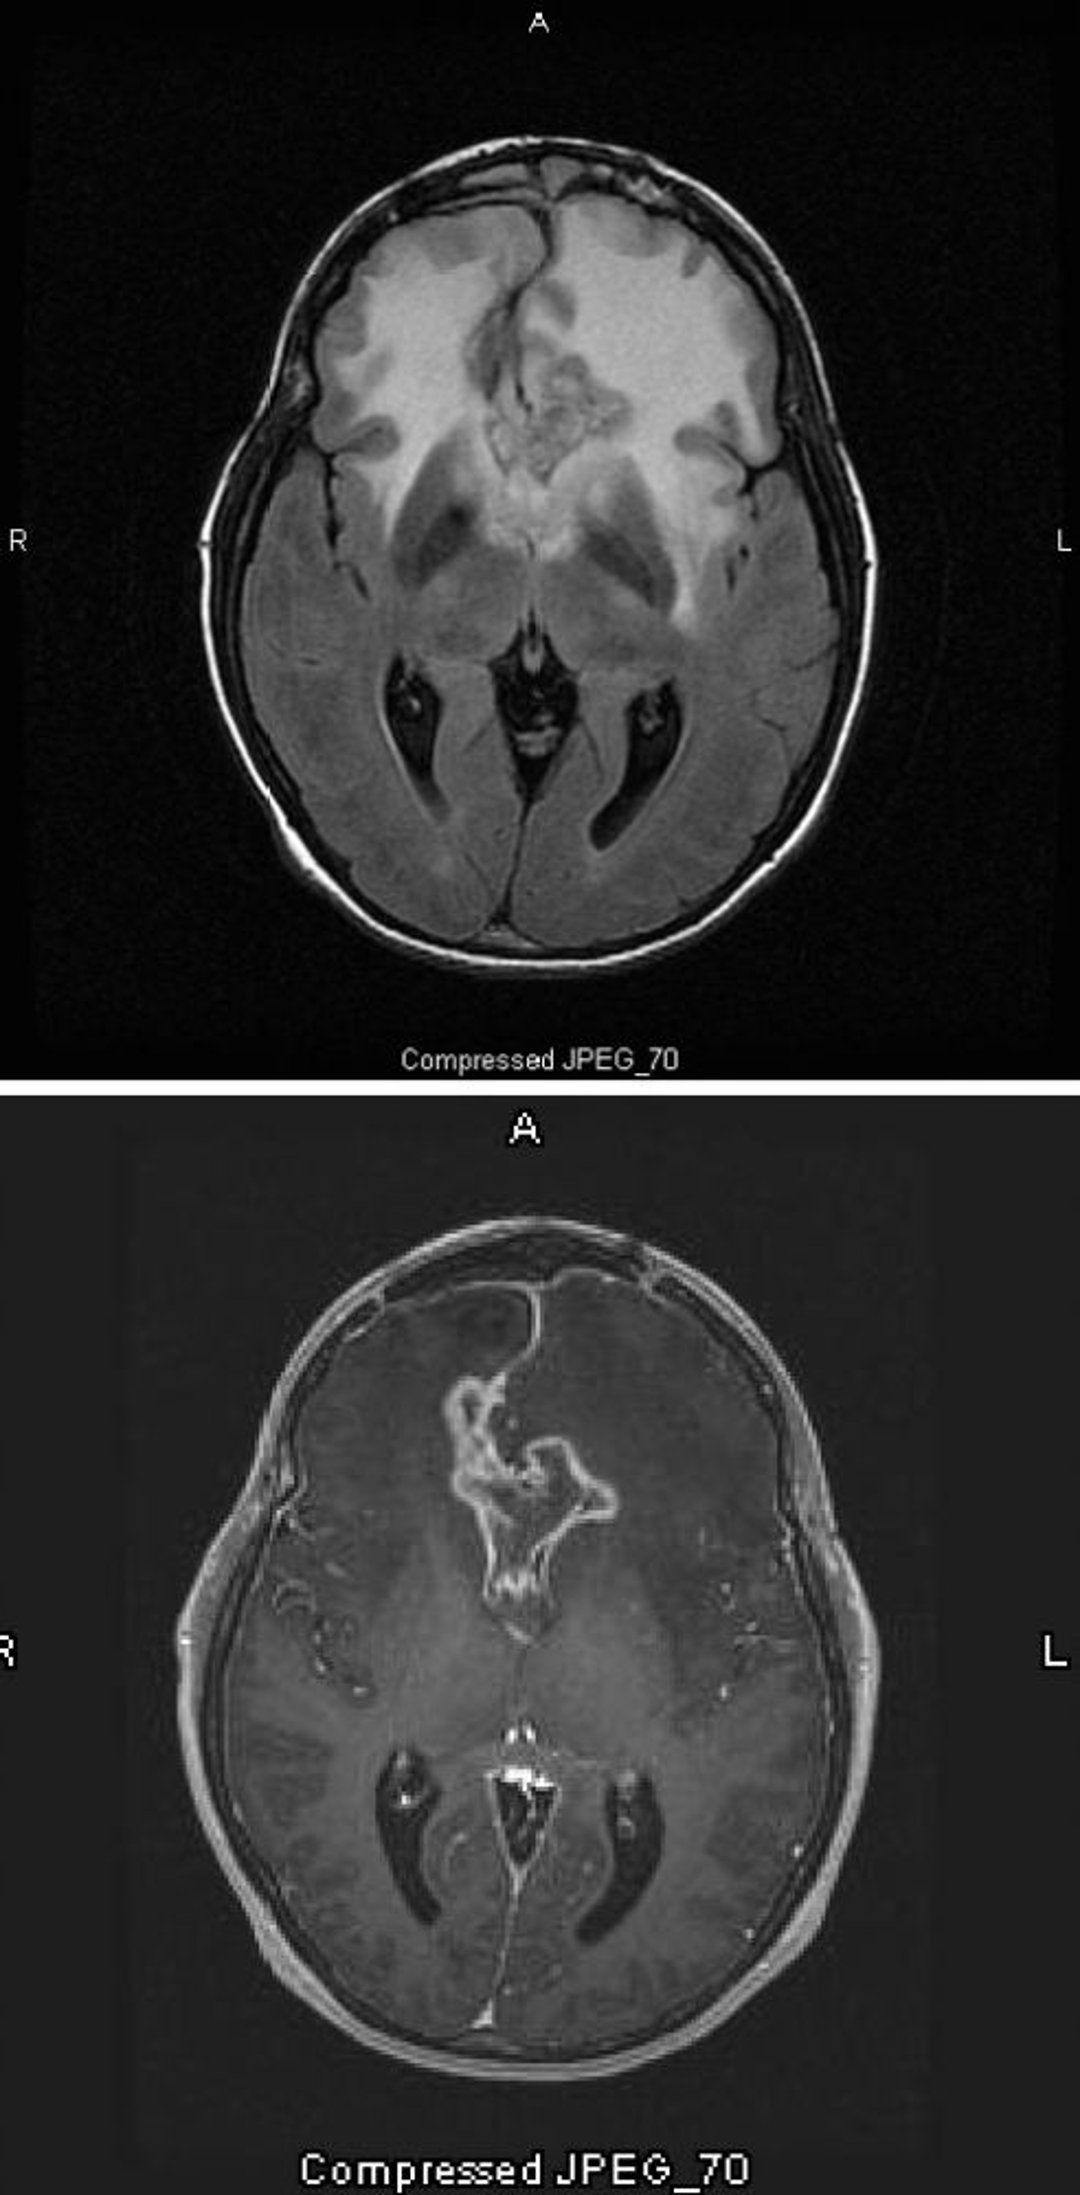

The T2-FLAIR MRI scan (top) shows a large, bilateral white (hyperdensity) signal around a glioblastoma, which is the highest grade and most malignant astrocytoma. This particular glioblastoma is called a butterfly glioma because the white signal around the tumor forms the wings of the butterfly; it is caused by cerebral edema. On the T1-weighted scan (bottom), contrast outlines the edge of the tumor (ring enhancement). The edema appears as a darkened area (hypointensity) on T1.

Images courtesy of William R. Shapiro, MD.